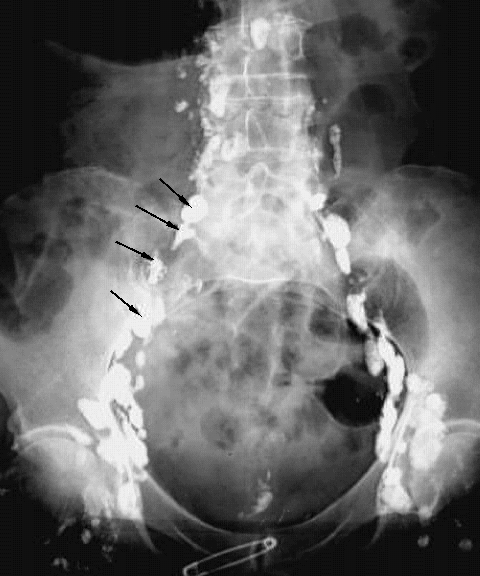

Abdomen - Lymphangiogram

Arrows: Common Iliac Lymph Nodes